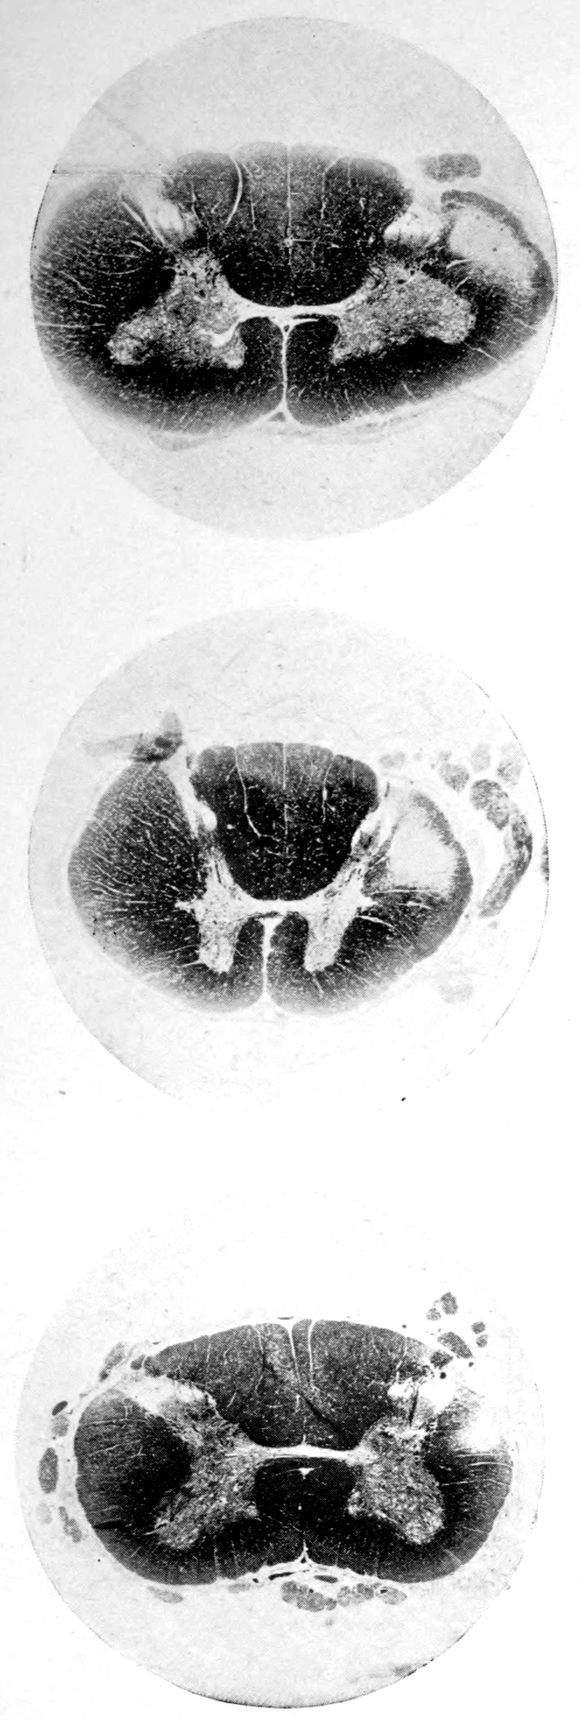

Case I. Spinal Cord (Three Levels) Showing:

A. Marginal sclerosis—effect of old meningitis now extinct.

B. Posterior column sclerosis—effect of meningitis about posterior roots also now extinct.

C. Bilateral pyramidal tract sclerosis—effect of cerebral thrombotic lesions.

Note distortion of tissues in B and C, partly artificial (tissues in places diffluent).

Case 4. (See previous figure for brain lesion.) Three levels of the spinal cord showing unilateral pyramidal tract sclerosis, 10 years after cerebral thrombosis.